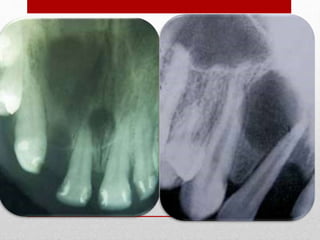

Imágen radiográfica. Observe en la línea media del maxilar superior en zona incisiva una imagen radiolúcida, bien definida y de forma

ovoidea.

QUISTE DEL CONDUCTO NASOPALATINO Imágenradiográfica. Observe en la línea media del maxilar superior en zona incisiva una imagen radiolúcida, bien definida y de forma ovoidea.